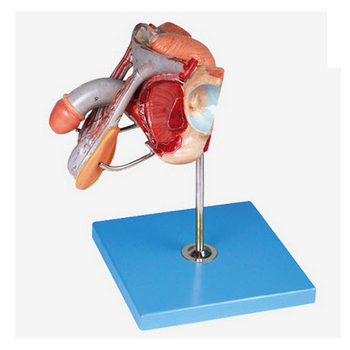

GD/A15102男性生殖器官結構模型產品介紹:1、型號規格:GD/A15102 2、名 稱:男性生殖器官結構模型3、品 牌:全科醫生4、簡 介:該模型由男性生殖器官、膀胱矢狀切面和陰莖橫切面...